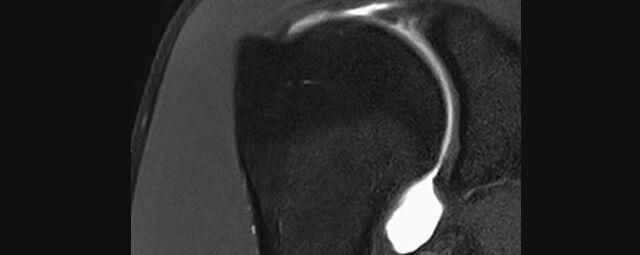

Arthrographie

• MR-Arthrographie – nach örtlicher Betäubung und gründlicher Desinfektion der Haut wird unter Lagekontrolle mit Röntgen-Durchleuchtung eine kleine Nadel in den Gelenkraum positoniert und darüber ein MR-taugliches Kontrastmittel in den Gelenkraum gespritzt. Danach wird die Nadel entfernt. Anschließend erfolgt die MRT des Gelenkes. Diese Methode stellt kleine anatomische Strukturen des Gelenkraumes verbessert dar, z.B. zur Therapieplanung vor Arthroskopie bei Sportverletzungen der Schulter oder Gelenkinstabilität.